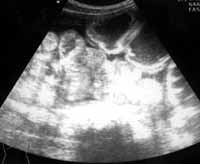

Кроме того, обращали внимание на состояние складок Керкринга: при локализации непроходимости в пределах тощей кишки складки ее оказались сохраненными (20), при локализации непроходимости в пределах подвздошной кишки слизистая петель последней оказалась лишенной складок (29). Чем ближе к месту обструкции, тем более было выражено утолщение стенок и складок за счет отека и наложения фибрина (Рис. 1–4).

[Увеличить]

Рис. 1. Эхограмма больного с механической тонкокишечной непроходимостью - спаечный процесс на уровне проксимальных отделов подвздошной кишки. При продольном сканировании на уровне тощей кишки отмечается внутрипросветное депонирование жидкости, расширение просвета тонкой кишки, утолщение складок.